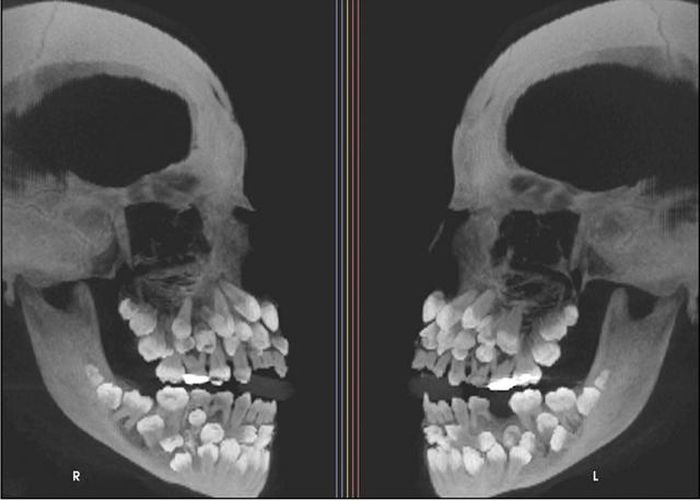

Đi nhổ răng sữa, một bé gái 11 tuổi đã khiến nha sĩ sốc nặng khi phát hiện phim chụp X-quang cho thấy cô bé có 81 chiếc răng trong miệng.

Các hãng thông tấn nước ngoài đã đưa tin về một trường hợp y khoa xảy ra ở Brazil, nơi một bé gái 11 tuổi đến gặp nha sĩ để nhổ răng sữa. Tuy nhiên, kết quả chụp X-quang cho thấy miệng bé có tổng cộng 81 chiếc răng, bao gồm 31 chiếc răng thừa. Trường hợp hiếm gặp này sau đó đã được đăng trên một tạp chí y khoa và trở thành chủ đề nóng hổi.

Cụ thể, bé gái 11 tuổi 8 tháng ở Minas Gerais, Brazil, đã đến một phòng khám nha khoa để kiểm tra răng miệng và dự định nhổ hàng răng sữa trên cùng vốn vẫn chưa rụng. Tuy nhiên, kết quả chụp X-quang cho thấy một phát hiện gây sốc, thực tế bé có 18 răng sữa, 32 răng vĩnh viễn và 31 răng thừa, tổng cộng là 81 răng.

Bé gái có 81 chiếc răng khiến nha sĩ bất ngờ.

Khi khám răng, bác sĩ nhận thấy chỉ có 5 răng vĩnh viễn đã mọc, trong khi vẫn còn khá nhiều răng sữa. Để đánh giá toàn diện hơn tình trạng răng miệng của bé, bác sĩ đã chỉ định chụp X-quang tổng quát và chụp sọ nghiêng.

Những hình ảnh cho thấy nhiều răng bị biến dạng và nằm sâu trong nướu, khiến việc phân biệt giữa răng bình thường và răng thừa rất khó khăn. Trung bình, một người trưởng thành có 32 chiếc răng và những chiếc răng thừa này được gọi là "siêu răng". Thông thường, chỉ có 1 hoặc 2 chiếc răng thừa.

Theo giải thích của các bác sĩ, răng thừa là một bất thường phát triển hiếm gặp, có thể xuất hiện ở bất kỳ vị trí nào trên cung răng và ảnh hưởng đến răng bình thường. Việc có nhiều răng thừa cực kỳ hiếm gặp ở những người không mắc các bệnh lý hoặc tình trạng di truyền khác.